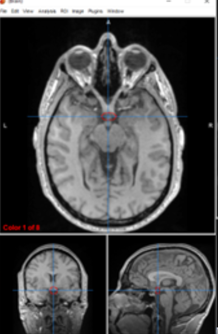

optic chiasm

separates visual input